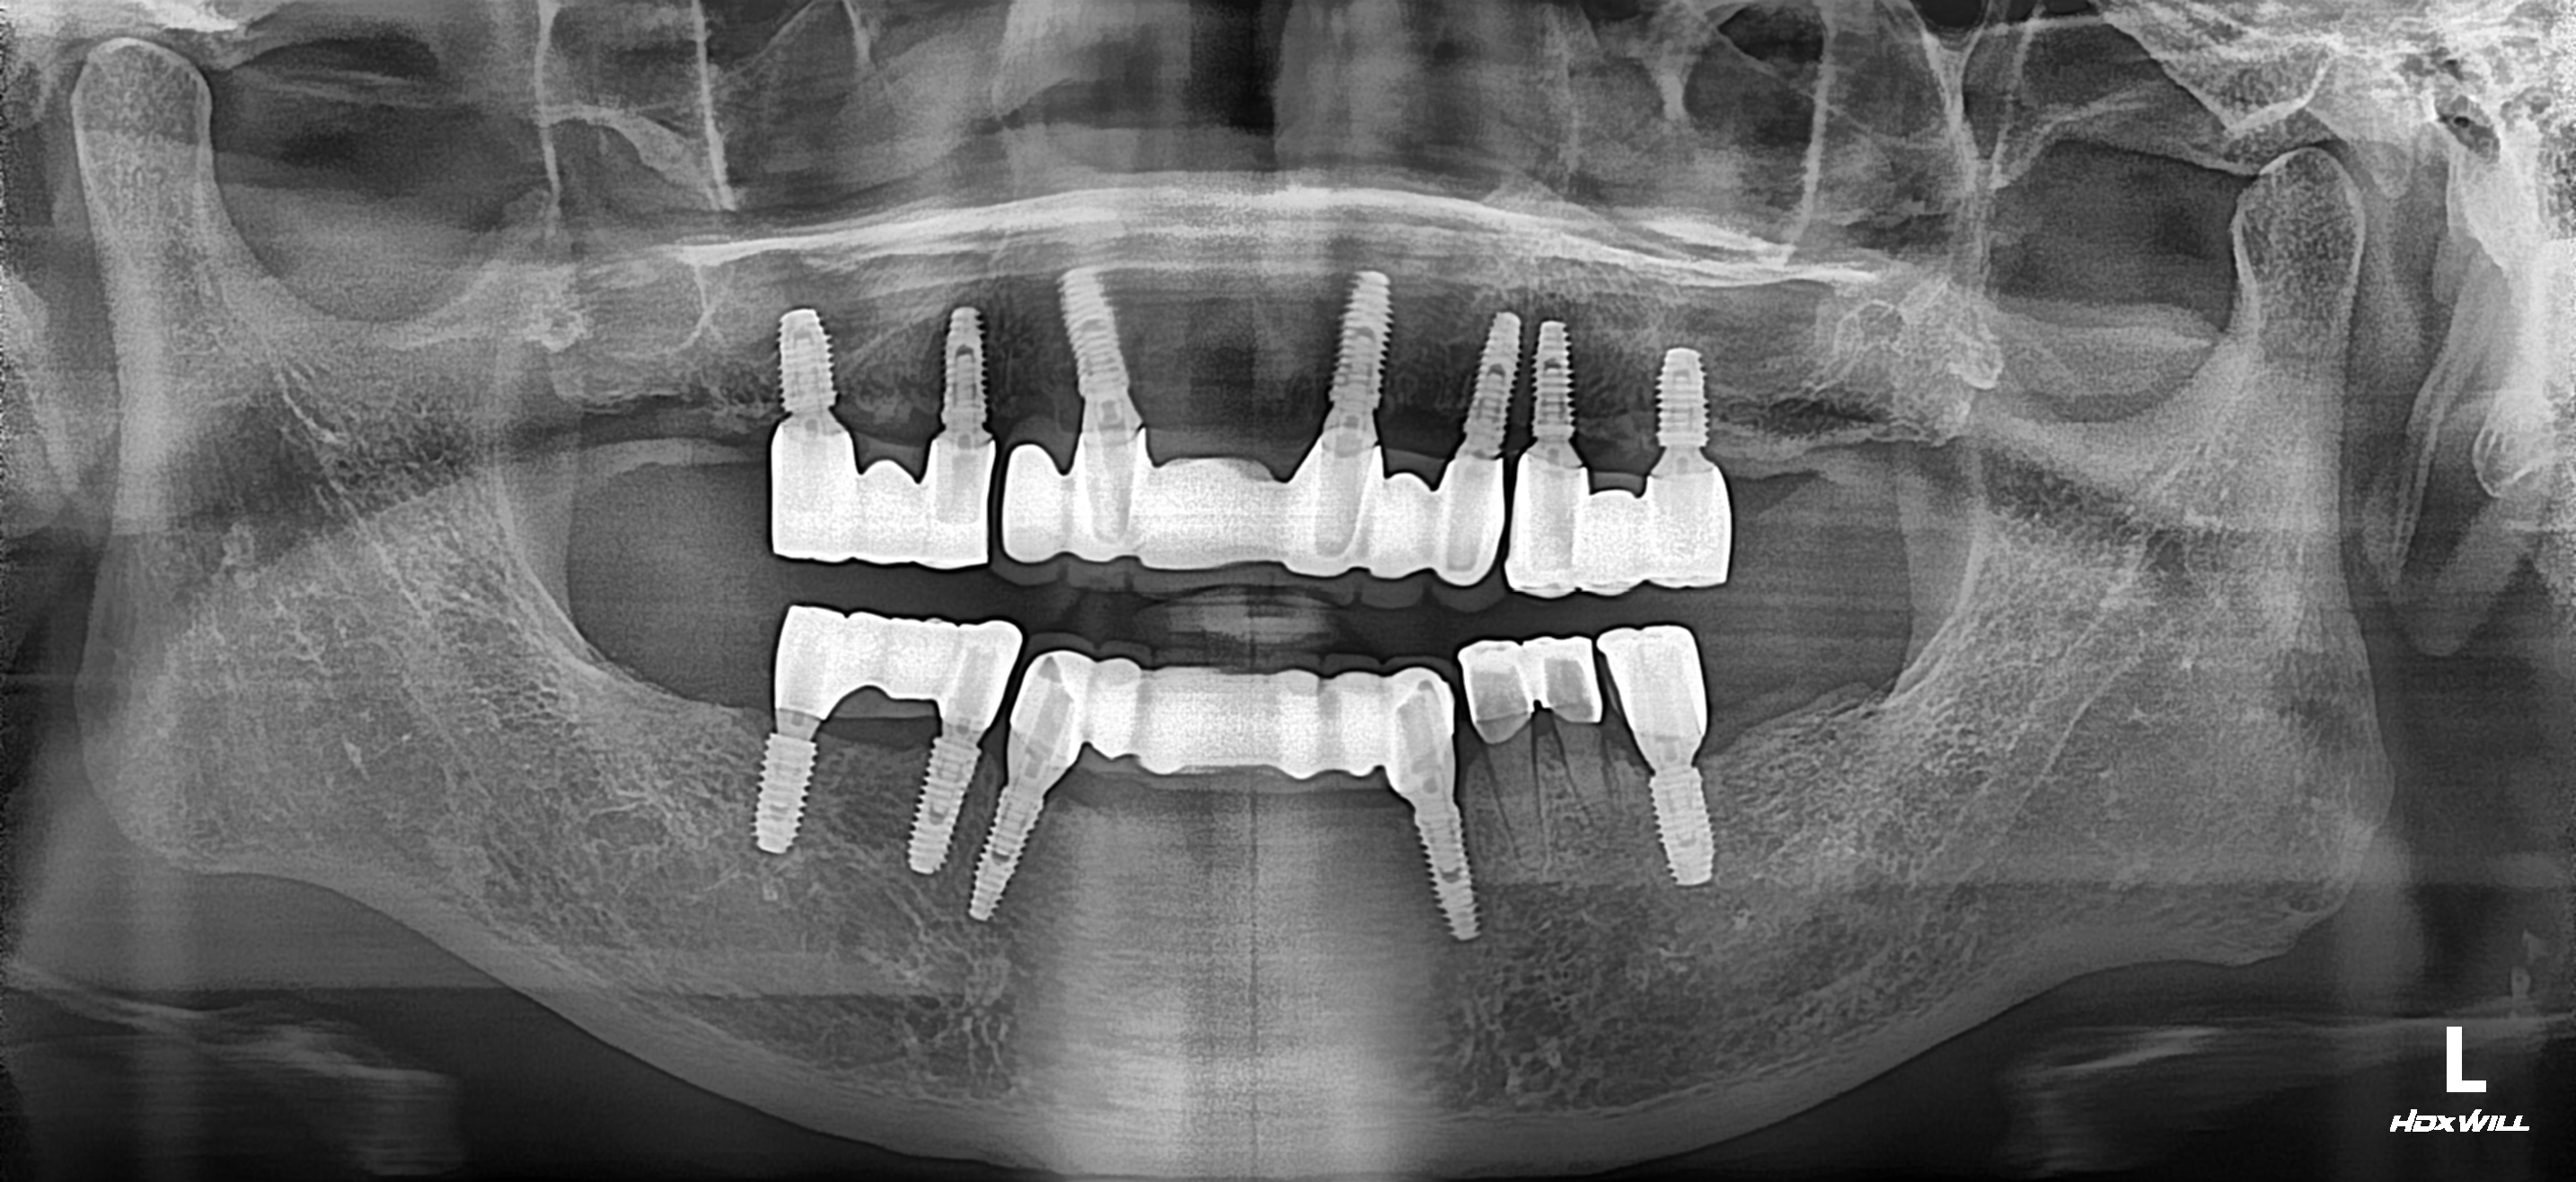

어려운 전악 임플란트 네비게이션 치료

"이가 다 망가져서 수원에 있는 치과갔는데 대…

어려운 전악 임플란트 네비게이션 치료 2022-01-18 "이가 다 망가져서 수원에 있는 치과갔는데 대학병원가라고 해서 왔어요."구강관리 부족으로 모든 치아가 치주염으로 흔들려서 내원하셨습니다.상악 구치부는 치조골이 거의 없어져 임플란트… |